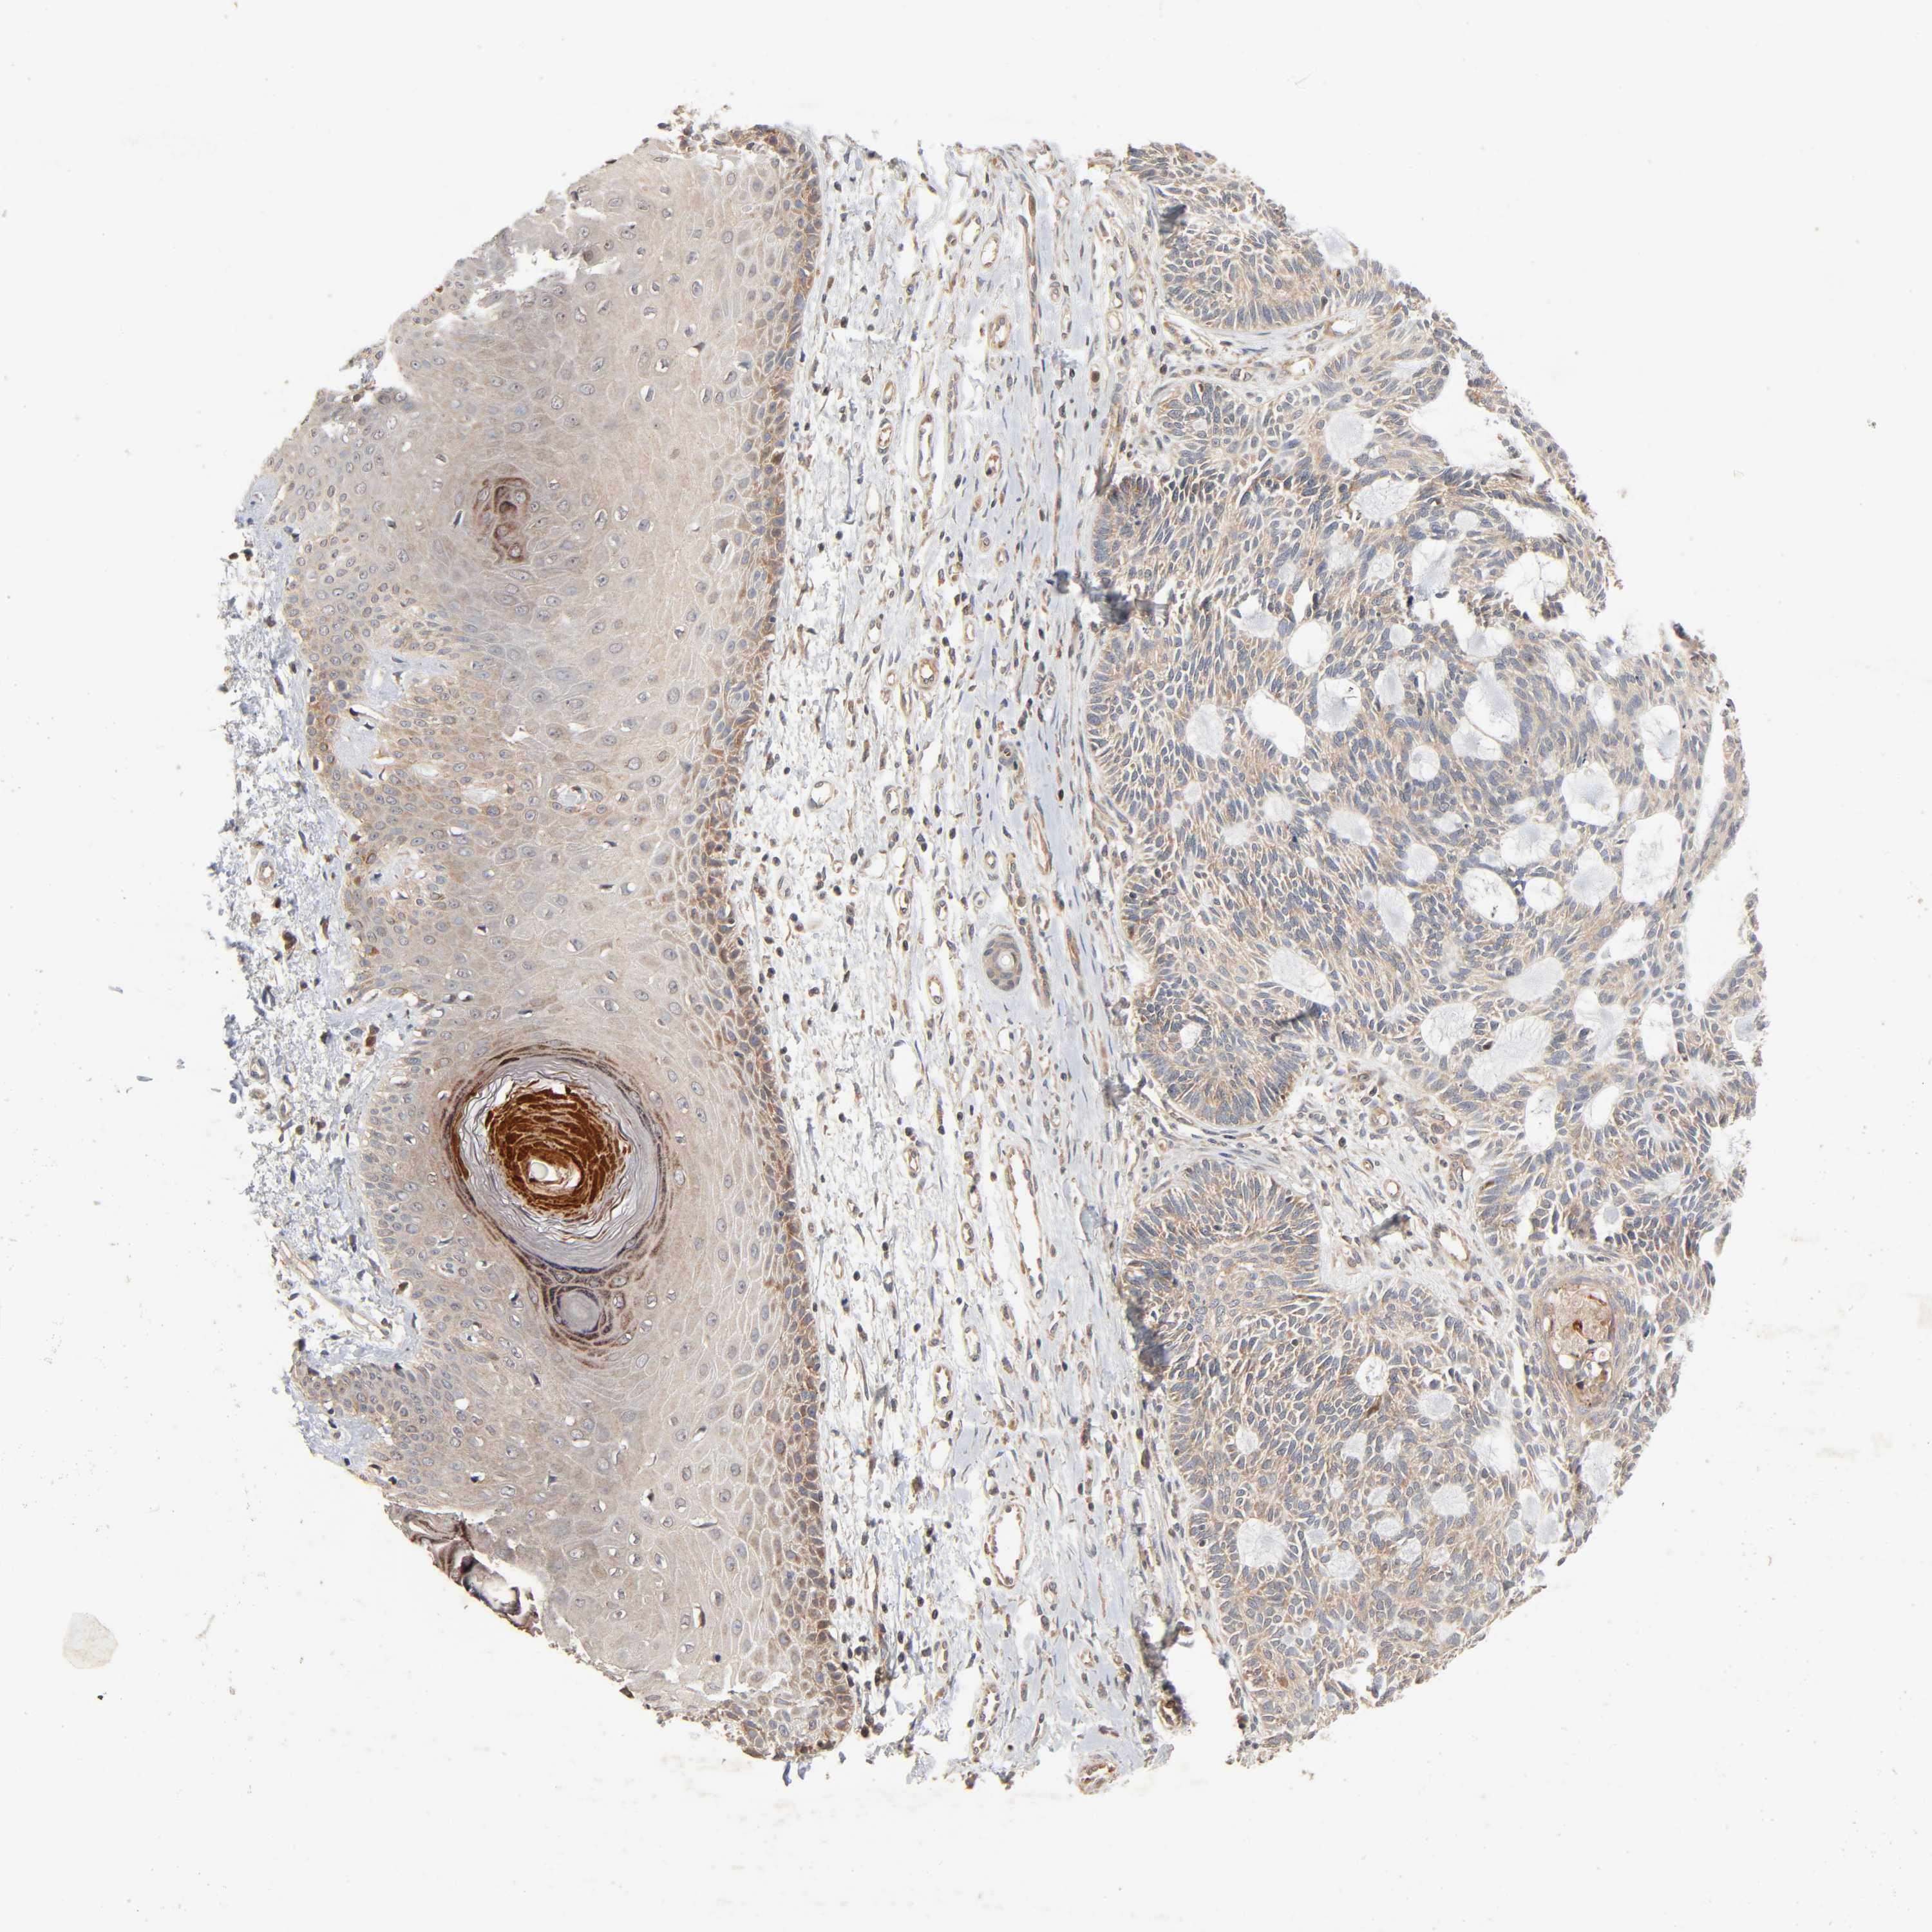

Basal cell and squamous cell cancer

SKIN CANCER - Protein expressioni

A mouse-over function shows sample information and annotation data. Click on an image to view it in a full screen mode. Samples can be filtered based on level of antibody staining by selecting one or several of the following categories: high, medium, low and not detected. The assay and annotation is described here.

Antibody stainingi

Antibody staining in the annotated cell types in the current human tissue is reported as not detected, low, medium, or high, based on conventional immunohistochemistry profiling in selected tissues. This score is based on the combination of the staining intensity and fraction of stained cells.

Each image is clickable and will lead to virtual microscopy that enables deeper exploration of all samples and also displays staining intensity scores, fraction scores and subcellular localization as well as patient and tissue information for each sample.

Antibody HPA004160

Staining

High

Medium

Low

Not detected

Intensity

Strong

Moderate

Weak

Negative

Quantity

>75%

75%-25%

<25%

None

Location

Nuclear

Cytoplasmic/membranous

Cytoplasmic/membranous,nuclear

Squamous cell carcinoma, NOS

Basal cell carcinoma